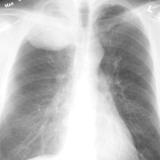

SCLC

Album: SCLC

Date: 10/01/2006

Size: 3 items

Views: 29952